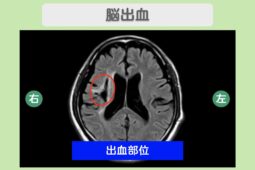

- 脳出血

脳出血後の看護ケアとは?家族ができること・退院後気をつけることを医師が解説!